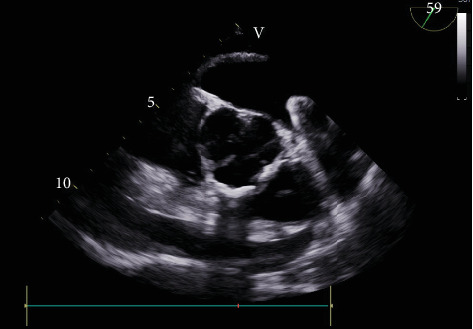

到2030年,美国将有超过1200万人患有心房颤动,这使中风的风险增加了五倍。Watchman装置是抗凝效果不佳的患者的一种选择。在此,我们报告一例罕见的左心耳(LAA)穿孔的Watchman装置植入病例,术中发现该装置部分位于心包间隙。一名93岁女性,有高跌倒风险,服用香豆素,接受瞭望者装置安置。植入过程中,发现LAA穿孔,部署过程中心包有收缩渗出,决定部署装置,希望它有助于密封泄漏。取出该装置被认为会使患者面临更大穿孔的风险。在此之后,成功的心包开窗术和临时引流术避免了胸骨切开,总体效果良好。一个自扩展框架覆盖左心房表面Watchman装置被部署,之后一个罕见的但潜在的并发症穿孔在分娩期间被注意到。留在原地的装置密封了泄漏,并防止了万一装置被取回时可能的恶化。最终,这个决定改善了病人的预后。

By 2030, the United States will have over 12 million people with atrial fibrillation, which carries a five-fold increase in risk of stroke. Watchman device is an alternative in patients who are poor candidates for anticoagulation. Here, we present a rare case of Watchman device implantation related to left atrial appendage (LAA) perforation noted intraoperatively with portion of the device in the pericardial space. A 93-year-old female with high fall risk and on Coumadin presented for Watchman device placement. During implantation, LAA perforation was noted with exudation of contract in the pericardium during deployment, and decision to deploy the device was made, hoping it would help seal the leak. Retrieving the device was thought to put the patient at risk of bigger perforation. Following which successful pericardial window with temporary drain placement avoided sternotomy and overall had a good outcome. A Watchman device with self-expanding frame covering the left atrial facing surface was deployed, after which a rare but potential complication of perforation was noted during delivery. The device left in place sealed the leak and prevented potential worsening incase device was retrieved. Eventually, this decision improved the outcome of the patient.